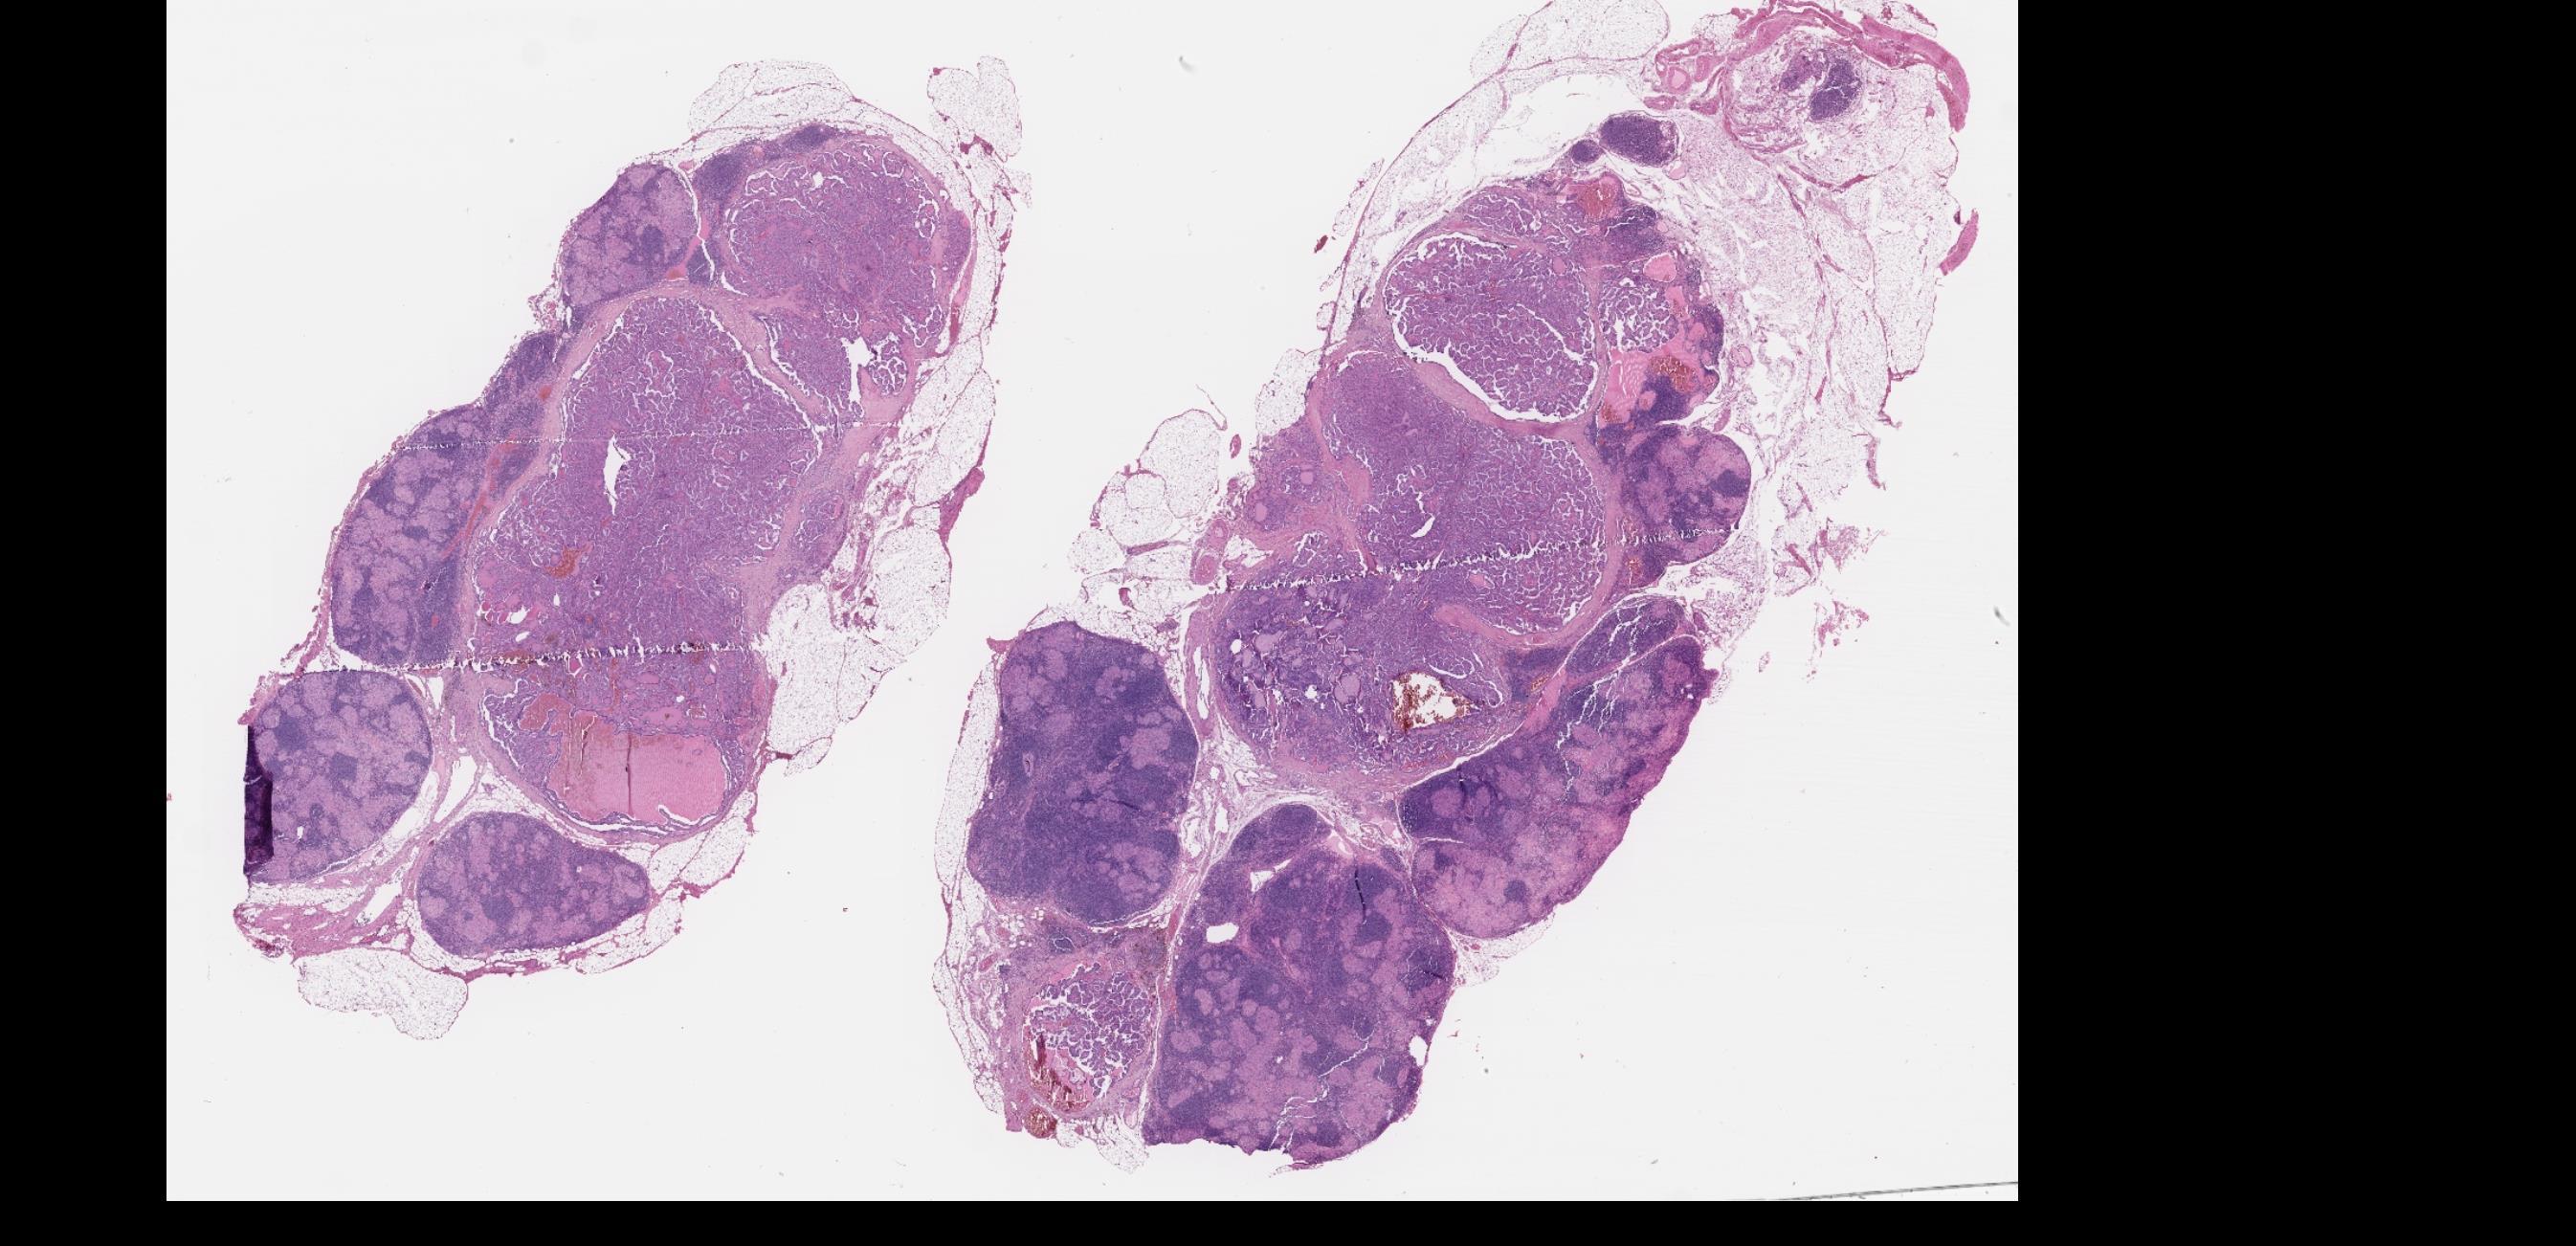

Case 12

Female 45 years Total thyroidectomy and bilateral neck dissection.

Case 12 Diagnosis

Papillary thyroid carcinoma, metastatic, in a background of granulomatous lymphadenitis